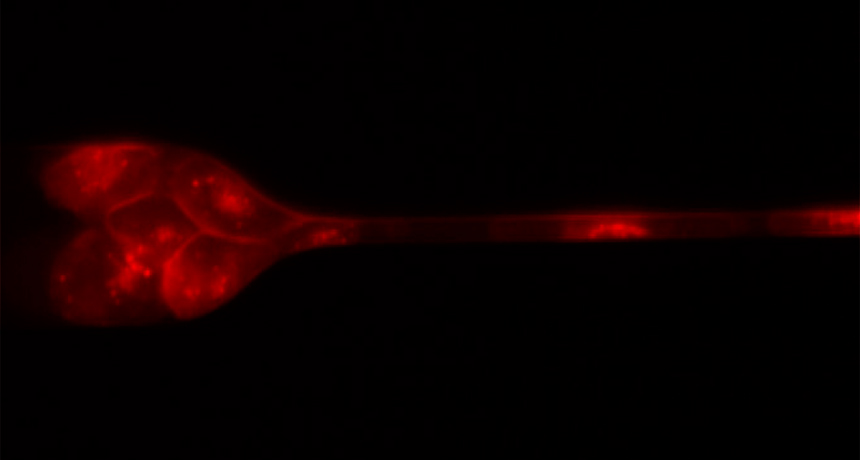

SQUEEZE PLAY As a clump of stained human breast cancer cells approaches a capillary tube, the cells adjust their formation and their shape to pass through the narrow space.

S.H. Auet al/PNAS 2016